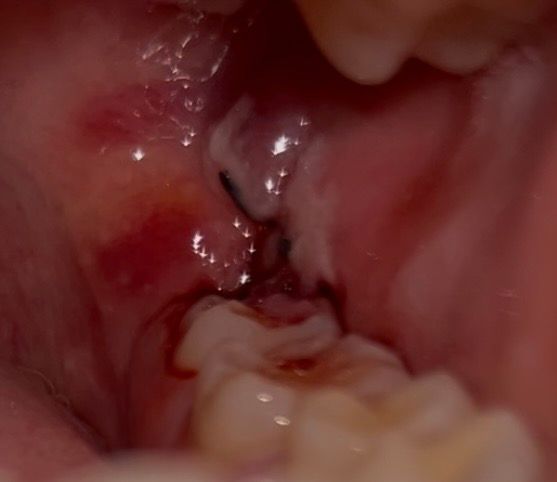

매복사랑니 발치 3일차 출혈 괜찮은건가요?

발치 3일차고 통증은 아직 있습니다 ㅠㅠ

피가 멈췄다가 코감기가 걸려서 재채기를 10분에 한 번씩 하더니 다시 피가 나기 시작합니다

• 1번 째 사진

피가 약간 나는 정도는 문제가 되지 않으며 사진상에서도 특별히 문제가 보이지는 않습니다.

3일차 이정도면 정상적으로 아물고 있는 것입니다. 자극에 의해 피가 조금 스며 나와도 문제되지 않습니다.

아직은 지혈이 완벽히 되는건 아닌거 같습니다. 피가 조금씩 나오는건 괜찮지만, 계속해서 흐르면 치과에 가셔서 후처치를 받아보시는게 좋을것같습니다.

발치 후 약간의 출혈은 1주일 까지도 있을 수 있습니다. 큰 문제는 없어보이고요. 사진상으로도 특별히 이상은 없어보입니다.